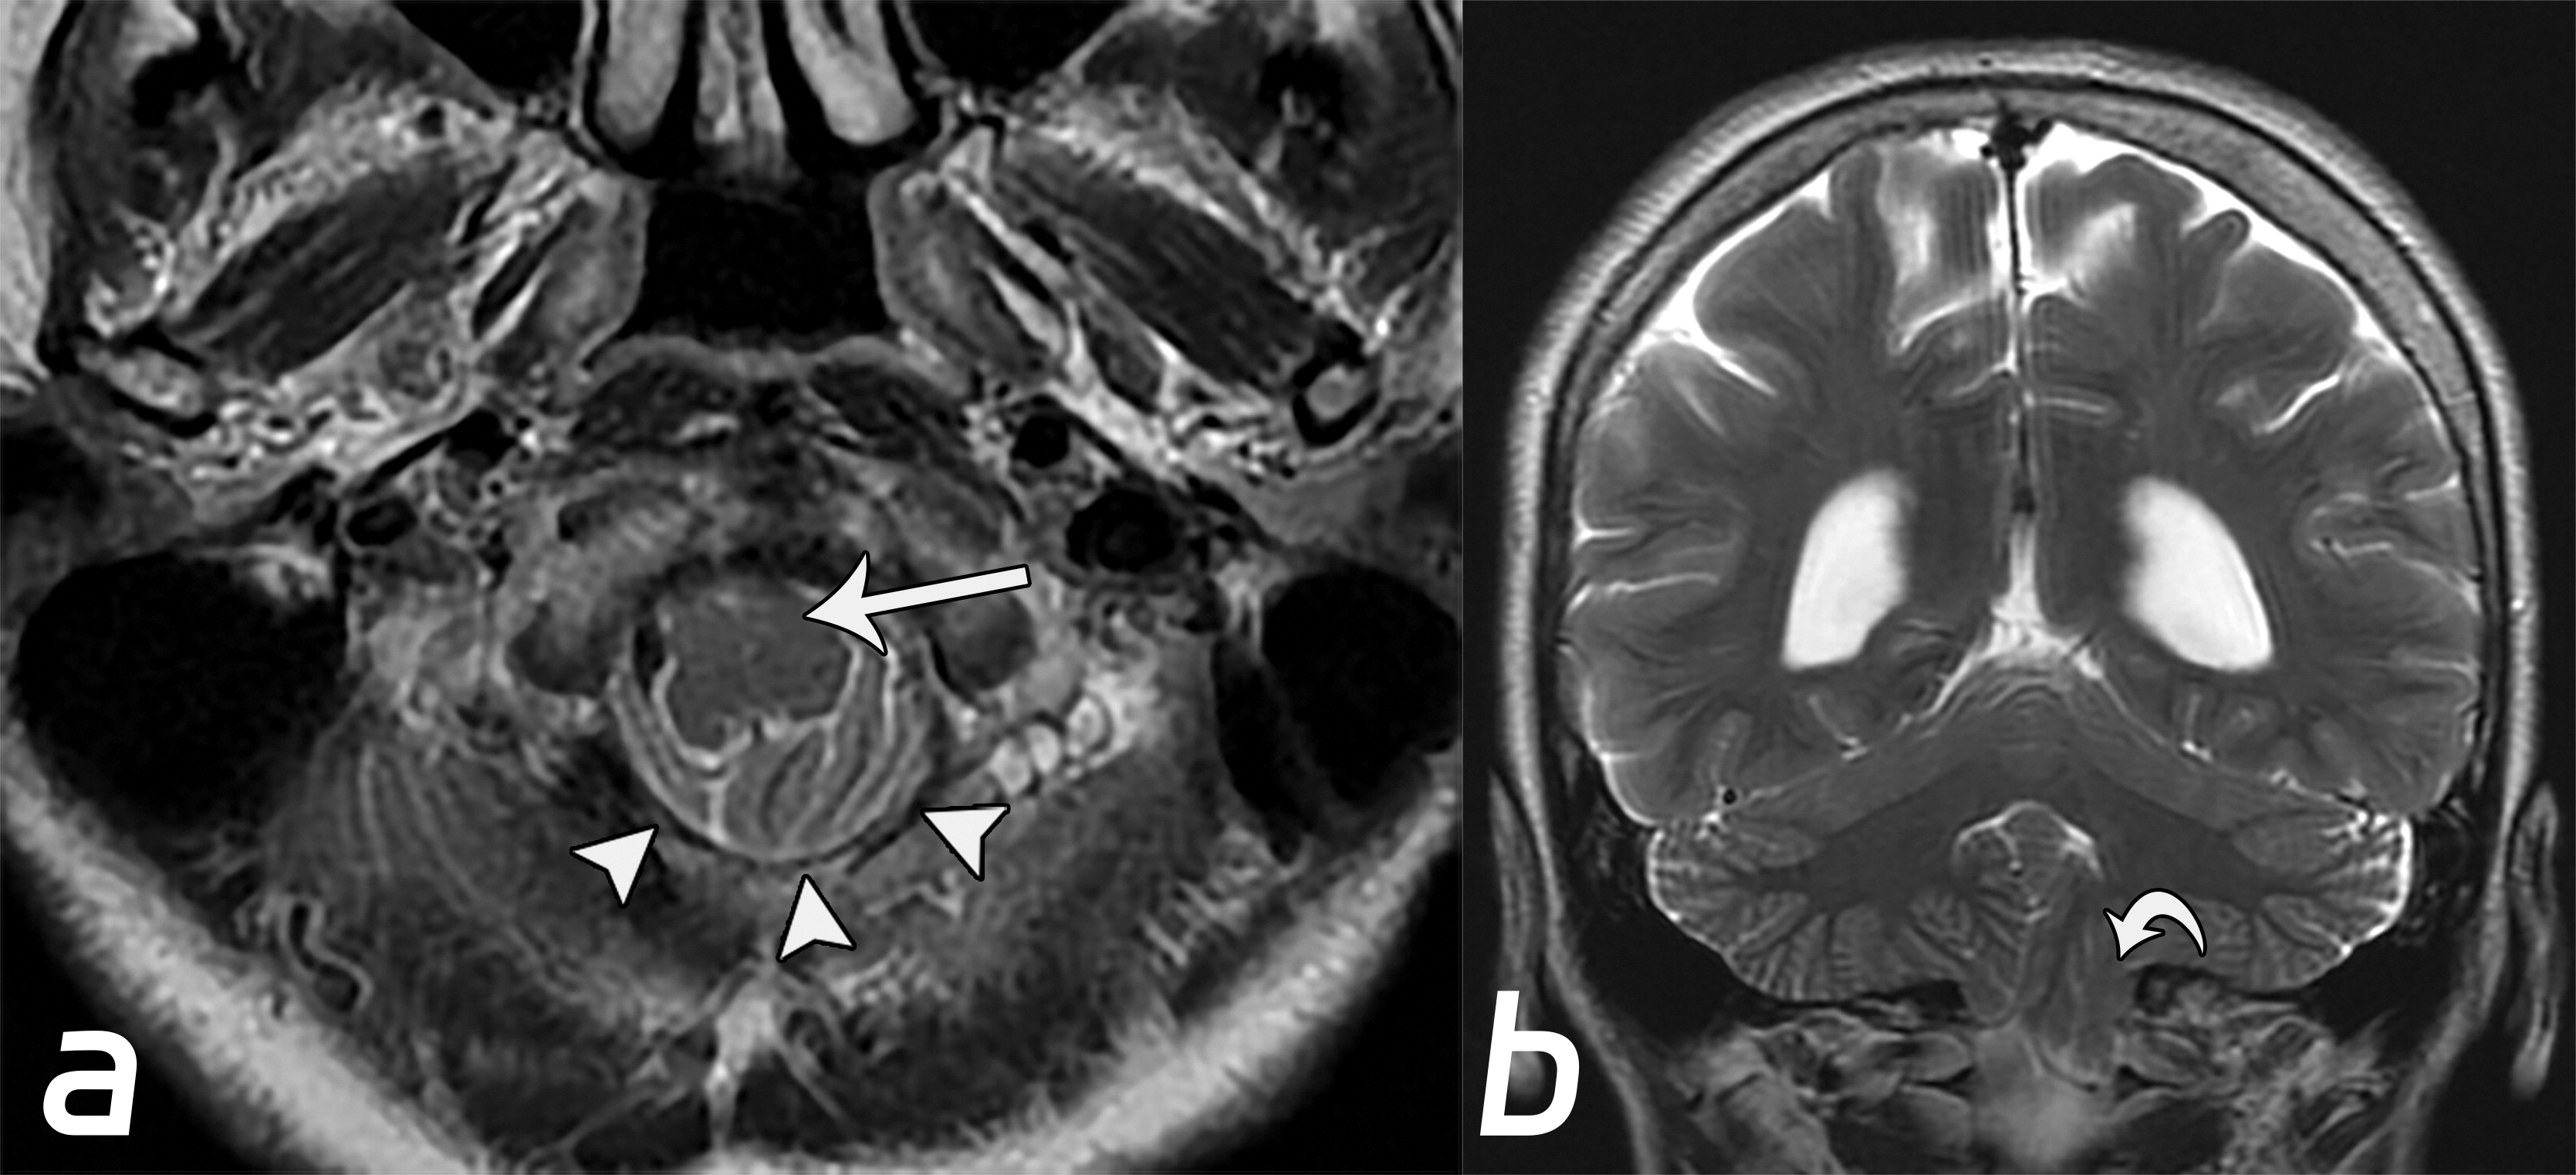

Chiari畸形Ⅰ型。小脑扁桃体下降(b图中白色弯曲箭头),伴脑干向前移位(a图白色长箭头),以及枕骨大孔脑脊液的闭塞(a图中白色短箭头)。